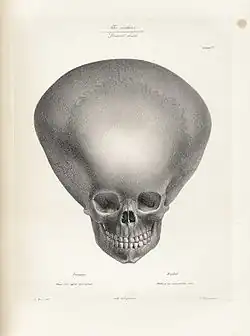

Hydrocephalus is difficult to detect clinically before delivery, although enlarged ventricles can be spotted on ultrasonography as early as 18–20 weeks gestation.[7] Since infants' skulls are not fully fused together at the cranial sutures yet, they have soft spots on their skulls known as open fontanelles.[8] This anatomic characteristic means that infants' skulls can visibly grow in size when cerebrospinal fluid accumulates. Therefore, infants with hydrocephalus may present with an enlarged skull (or rapid growth in skull size), bulging fontanelles, or separated cranial sutures.[8][9] Parents or physicians may also note that the infant is more irritable or tired than normal. Other symptoms include seizures, inability to look upwards ("sunset eyes" or "setting sun" sign), and pauses in breathing.[8][9] Infants may also present with lack of weight gain or failure to meet motor and developmental milestones.[10] Imaging can be done to confirm the suspected diagnosis of hydrocephalus. In infants, the open fontanelles allow for use of head ultrasonography. This allows pediatricians to minimize radiation exposure and come up with a diagnosis quickly.[8] If further information is needed, an MRI can be done.[7]

Mechanism of symptoms

When the cerebrospinal fluid builds up, it causes compression of the brain, which leads to the symptoms of convulsions, intellectual disability, and epileptic seizures. These signs occur sooner in adults because their skulls are no longer able to expand to based on the increasing fluid volume. Fetuses, infants, and young children with hydrocephalus have head enlargement, excluding the face, because the pressure of the fluid causes the individual skull bones—which have yet to fuse—to bulge outward at their juncture points.[39]

CSF can accumulate within the ventricles, a condition called internal hydrocephalus. It may result in increased CSF pressure. The production of CSF continues, even when the passages that normally allow it to exit the brain are blocked. Consequently, fluid builds inside the brain, causing pressure that dilates the ventricles and compresses the nervous tissue. Compression of the nervous tissue usually results in irreversible brain damage. If the skull bones are not completely ossified when the hydrocephalus occurs, the pressure may also severely enlarge the head. The cerebral aqueduct may be blocked at the time of birth or may become blocked later in life because of a tumor growing in the brainstem.[43]